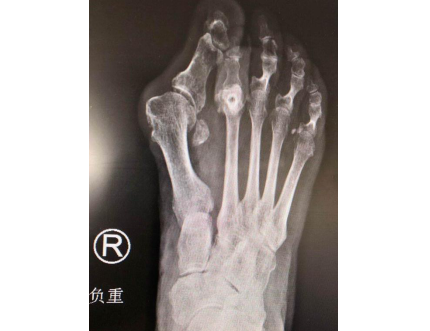

张奶奶术前(左图)术后(右图)

第二天,曹广超主任赵亮医生手术小组又为张奶奶进行了右足第2跖骨Weil截骨、第2趾近趾间关节成形,拇外翻截骨矫形内固定(第一跖趾关节融合)手术。